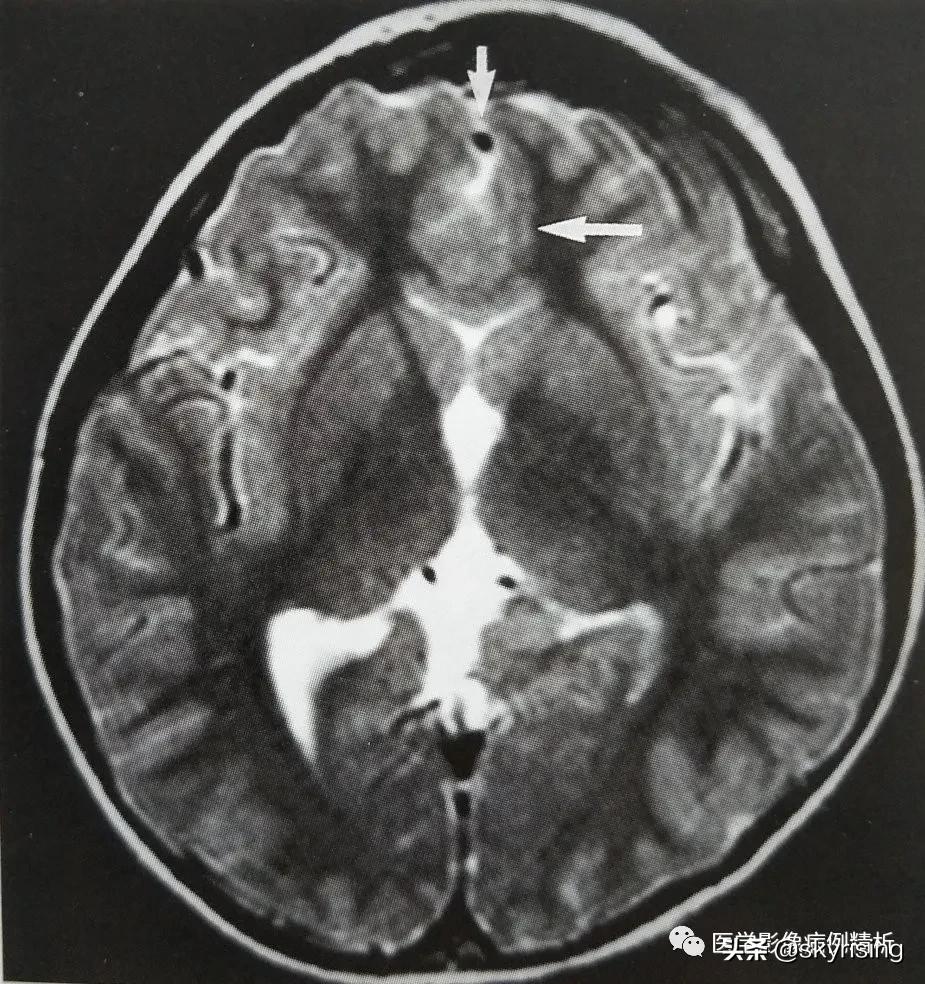

T1WI矢状位:红色箭头所示胼胝体嘴部、膝部、体前部缺如,正常扣带沟形态消失,双侧额叶延伸至侧脑室内。

T1WI轴位像:黄色箭头所示可见大脑前纵裂缺如,双侧额叶脑实质融合,胼胝体膝部未见显示。透明隔缺如,双侧侧脑室融合呈蝙蝠翼样改变。侧脑室额角未见显示,体部平行于矢状线,后角失去张力、变尖。

黄色箭头所示为大脑前动脉单支血管影,被推移至融合脑实质前。枕角形态尚可。双侧额部蛛网膜下腔增宽,见细带状液体信号,提示硬膜下积液。

红色箭头所示为融合额叶脑实质,大脑纵裂不完全。白色箭头所示为双侧视神经,形态对称、大小、信号未见异常,提示视神经发育正常。

MR影像表现,双侧额叶呈实质融合,大脑前纵裂缺如,后纵裂存在,胼胝体嘴部、膝部、体前部缺如,体后部及压部存在。本例即此型。